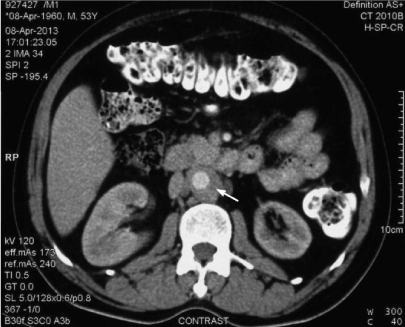

A 53-year-old male presented with low backache of 3 month’s duration. The pain was of moderate intensity, unaffected by motion, and not relieved by bed-rest. He had lost approximately nine kilograms over the last 6 months. He did not give any history of fever. Physical examination revealed blood pressure of 200/110 mm Hg in upper limbs and 180/110 mm Hg in both lower limbs. The remainder of physical examination was essentially normal. Blood investigations revealed elevated erythrocyte sedimentation rate of 130 mm and elevated C-reactive protein. Renal and liver function tests were essentially normal. Autoimmune (ANA, ANCA) and infectious work-up (serological testing for syphilis) were negative. Chest and lumbar spine radiographs were normal. A computerized tomography (CT) scan of the lumbar spine was undertaken to exclude any inflammatory process which showed retroperitoneal soft tissue thickening. Hence, CT angiography of aorta (Figure 1) was done which revealed extensive abdominal aortic thickening without any abnormal dilatation. In addition, there was a retroperitoneal concentric periaortic soft tissue mass (rind of periaortic tissue) causing luminal narrowing of the abdominal aorta and significant ostial stenosis of the left renal artery. Infectious work-up for vasculitis was also negative. There was no ureteric obstruction or hydronephrosis. This presentation was consistent with the diagnosis of isolated periaortitis confined to abdominal aorta. He was started on antihypertensives and steroids (prednisone 60 mg daily). On follow-up after 12 months, his blood pressure was controlled (130/80 mm Hg). Repeated CT scans showed progressive resolution of the periaortic rind with no evidence of abdominal aorta aneurysm.

Figure 1. CT abdomen revealed extensive aortic thickening without any abnormal dilatation